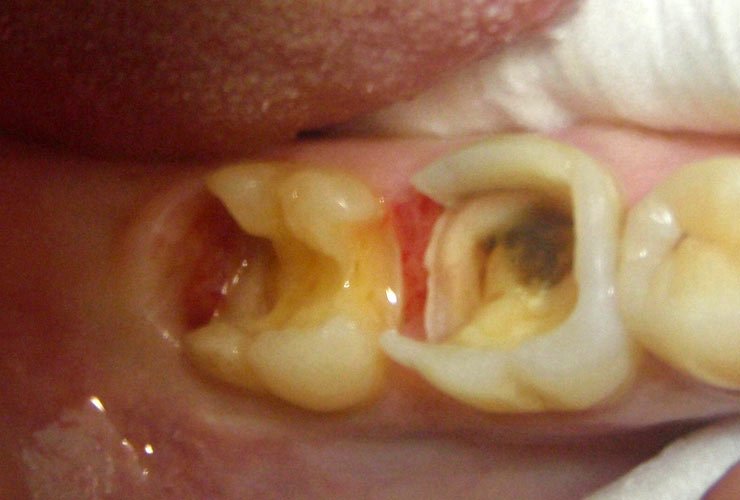

Фото

Кариес вызывает тревогу и беспокойство. Многие ищут рекомендации в интернете или у знакомых. Одни советуют немедленно записаться к стоматологу, чтобы избежать осложнений, другие предлагают временно использовать зубную пасту с фтором или специальные пломбы для замедления разрушения зуба. Однако только квалифицированный стоматолог может правильно оценить ситуацию и предложить эффективное лечение. Не откладывайте визит к специалисту: здоровье зубов связано с общим состоянием организма. Чем быстрее вы получите помощь, тем меньше вероятность серьезных проблем в будущем.

- Глубокий кариес. Запущенная форма заболевания приводит к постоянным болям, особенно ночью. Полость увеличивается, затрагивая глубокие ткани, включая нерв и корень зуба. Воспаление может привести к пульпиту или периодонтиту, иногда наблюдаются кровоточивость, отек щеки или выделение гноя.

- Средний кариес. Разрушение затрагивает дентин. Образуется дырка, в которую попадают остатки пищи, вызывая неприятные ощущения. Боль становится более частой, но связана только с механическим воздействием. Если временно закрыть дырку, она может не проявляться.